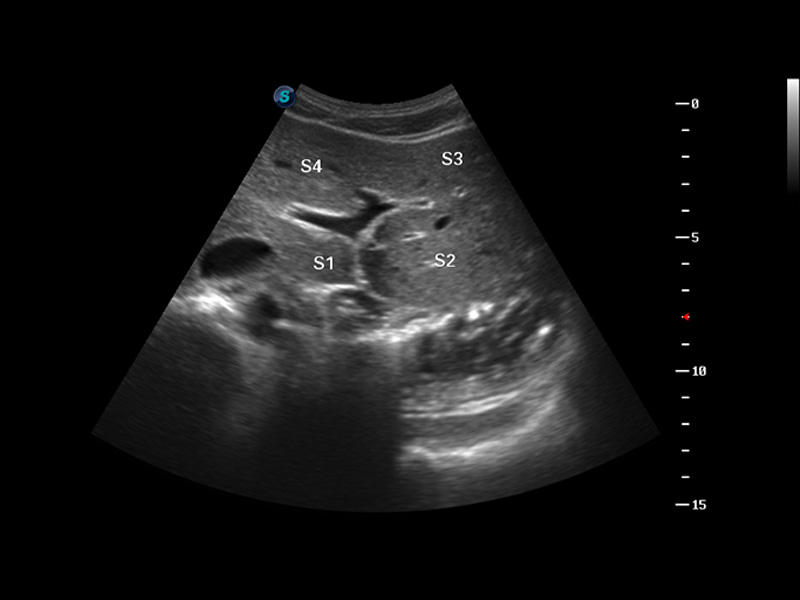

S8 EXP便携式彩色多普勒超声诊断仪是美狮贵宾会官网研发的高端全身应用型便携彩超。高通道的VIS平台融合可视化(Visual)、智能化(Intelligent)和人性化(Smart)的特点,配以美狮贵宾会官网自主研发生产的探头大家族,使您能够快速、准确的获得病人信息,提高工作效率的同时减轻疲劳。

成像技术

多波束形成器

μ-Scan微米成像

谐波成像

实时宽景成像

空间复合成像

3D/4D成像